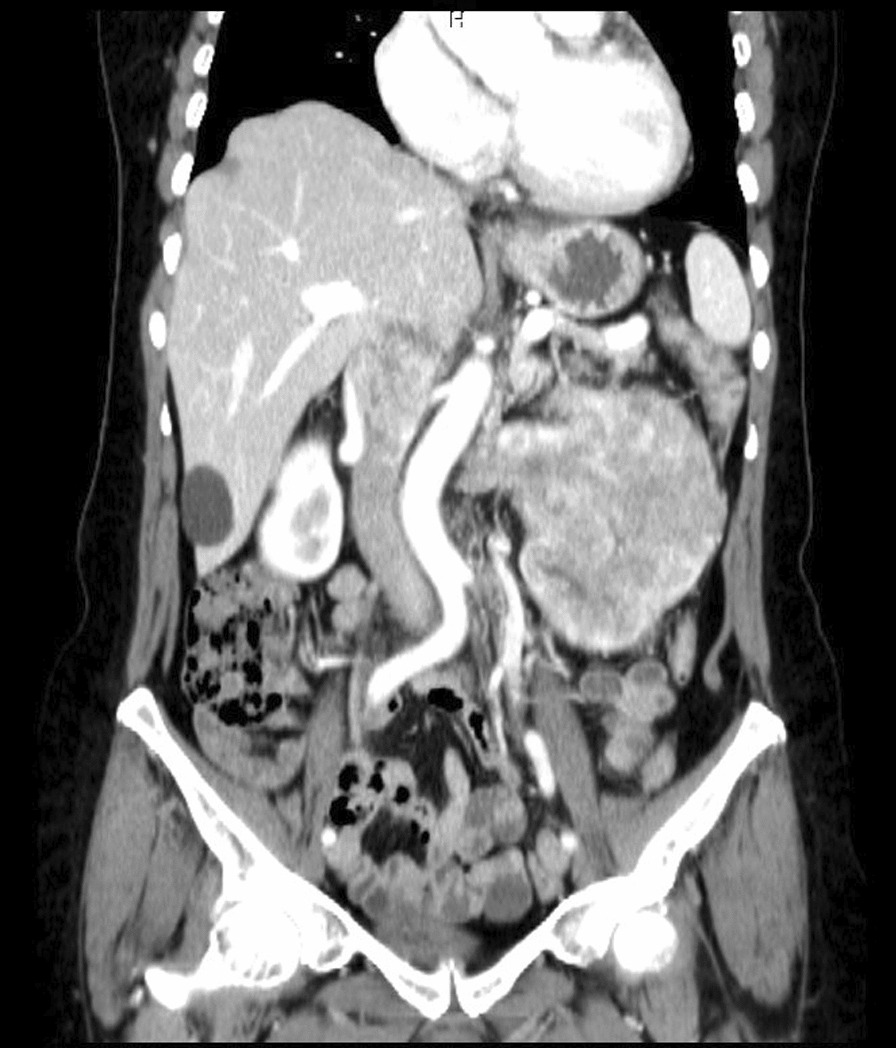

Fig. 1.

Preoperative computed tomography angiography, coronary view

After a comprehensive assessment, which included urine analysis, complete blood count, electrolytes, renal and hepatic function tests, as well as ultrasonography and computed tomography, she was diagnosed with left kidney renal cell carcinoma involving the left renal vein and subhepatic inferior vena cava (Figs. 1, 2). All tests came back normal, except for microhematuria and slight hypoalbuminemia. A minor increase in C-reactive protein was also noted (Table 1).

Fig. 2.

Preoperative computed tomography angiography, sagittal view